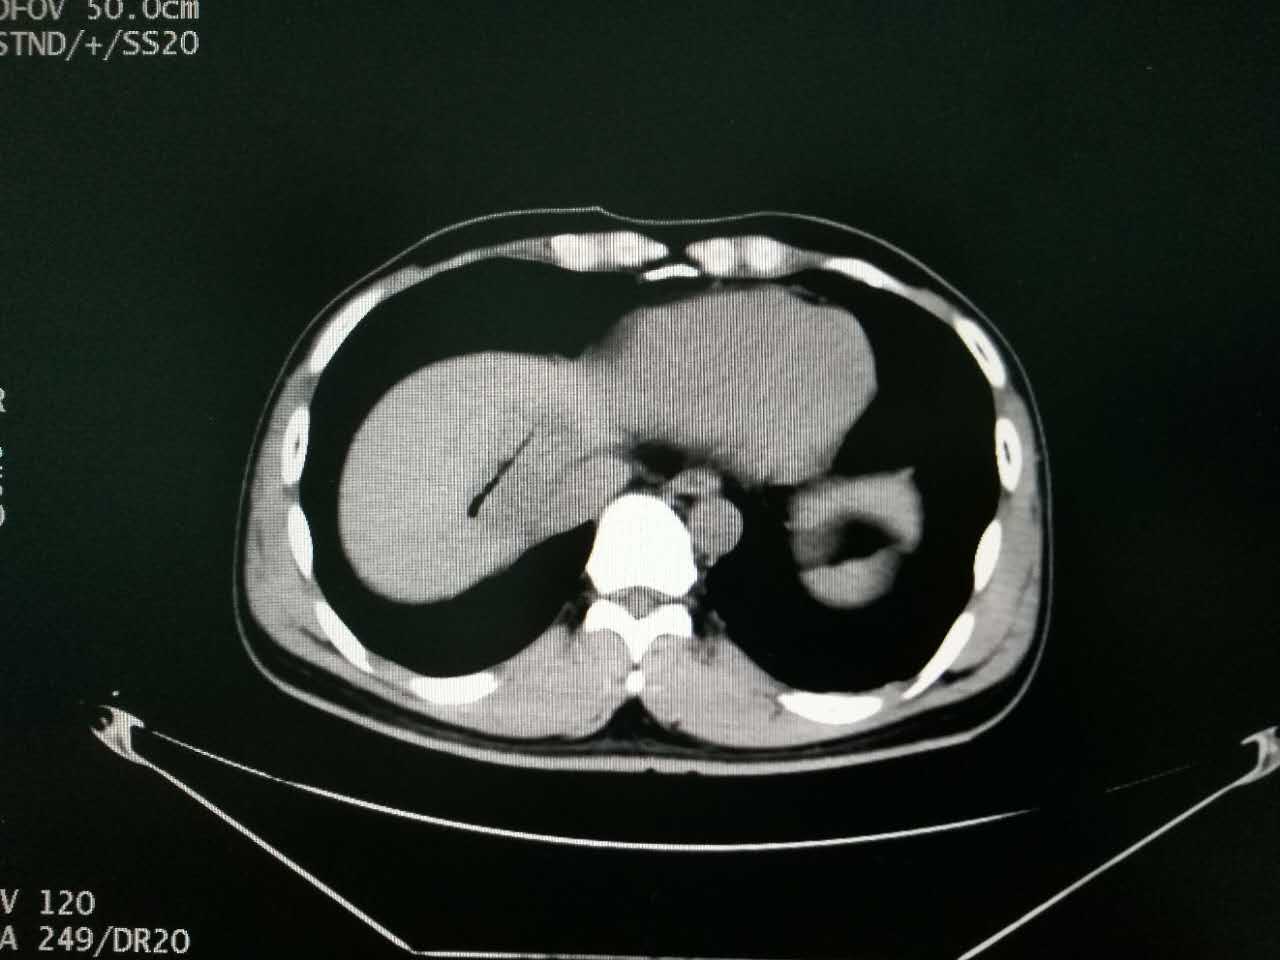

▲术后CT扫描见肿瘤消融完全